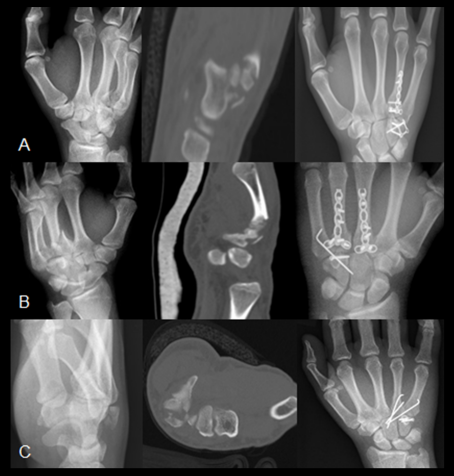

Figure 4 [Fig. 4] shows three radiological series, consisting of one exemplary pre-operative x-ray image, pre-operative CT image, and the post-operative final x-ray. Patient A was treated with a grid plate, patient B via K-wire osteosynthesis and patient C got a screw osteosynthesis of the hamate body.

Figure 4: Three patients with coronal hamate’s fracture (A – grid plate OS, B – K-wire and screw OS, C – screw OS). From left to right: preoperative x-ray, preoperative CT scan, postoperative x-ray